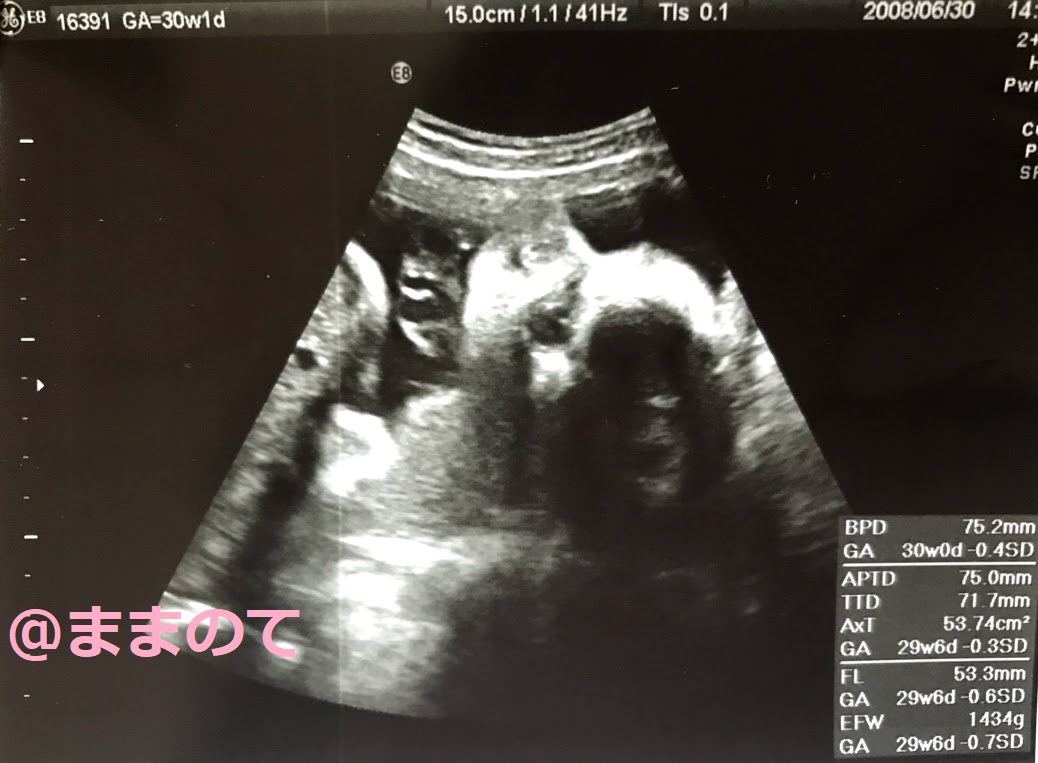

妊娠30週の赤ちゃんのエコー画像

妊娠30週1日のエコー画像です。体重1,434g、BPD7.5cmに成長しています。エコー画像には全身が入りきらず、頭部から胸にかけてが写し出されています。横顔から、頭の丸み、目、鼻が確認できますね。